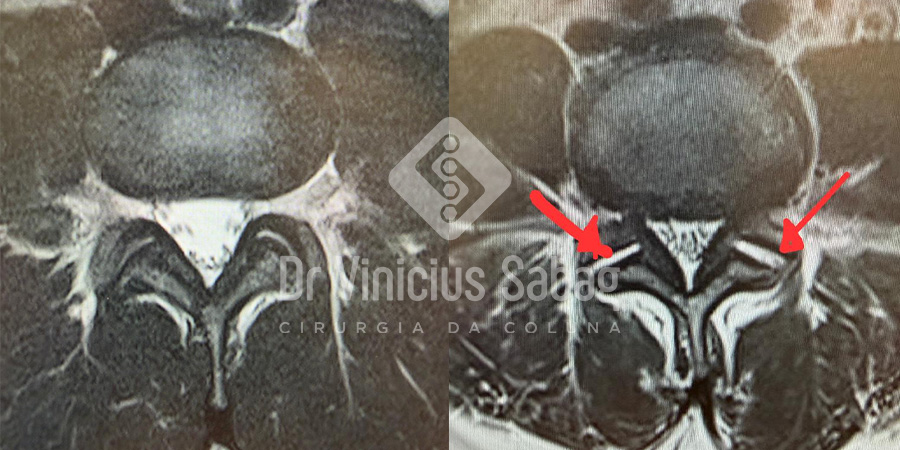

Ressonância magnética evidenciando a esquerda facetas articulares normais e a direita degeneradas (setas vermelhas).

Diagnóstico

- Exames de imagem: tomografia e ressonância magnética.